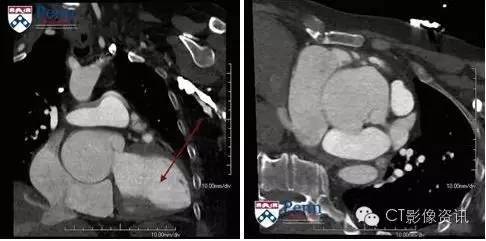

1. 图中箭头所指的部位是? 右心房 3票 2% 右心室 13票 9% 左心房 13票 9% 左心室 117票 80%

2. 这是一个需要心电门控的检查?

3. 异常的位置是在? 窦管交界处 32票 22% 右冠状动脉窦 41票 28% 左冠状动脉窦 44票 30% 无冠状动脉窦 29票 20%

4. 患者出现的心脏瓣膜杂音最有可能与下列何种原因有关? 主动脉瓣狭窄 16票 11% 主动脉瓣关闭不全 114票 78% 二尖瓣狭窄 8票 6% 二尖瓣关闭不全 8票 6%

5. 当患者出现下列何种情况时需进行手术治疗? 冠状动脉轻度压迫无心肌缺血 6票 4% 尺寸大于3厘米 89票 61% 出现心律失常 38票 26% 轻度主动脉瓣关闭不全 13票 9%

表现 回顾性心电门控冠脉CTA,可从79%期相的舒张末期图像中显示出主动脉根部扩大继发于非冠状窦瘤。扩大的窦口长径约6.4cm、横径约4.1cm。整个主动脉根部大小约6.9×7.3cm。

最终诊断:主动脉窦瘤--非冠状动脉窦